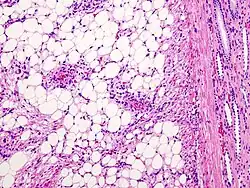

Mikroskopisch sind reife Fettzellen und glatte Muskelzellen nachweisbar. Die Muskelzellen können zahlreiche Mitosen aufweisen, daher kann der Tumor als Sarkom fehlgedeutet werden. Zusätzlich finden sich atypische Blutgefäße.